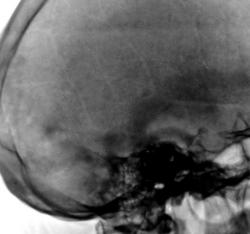

Представлены, на диске, такие изображения черепа. Что посоветуете уважаемые коллеги?

Уважаемый  Валентин Львович, я так понимаю Вас смущает ячейки лобной пазухи? В данном случае надо обратить внимание на толщину костей крыши черепа, а следовательно и на турецкое седло, следует проконсультироваться у эндокринолога с дальнейшим проведением МР-исследования гипофиза.

Структура затылочной кости не совсем обычная...похоже на "пробойниковые отверствия"...касаемо лобных пазух - такой "фасон", мне кажется это природа, и мало вероятно, что ендокринология...

Кости свода толстоваты, пазухи крупные. Турецкое седло не изменено. По-моему, стоит беспокоиться, только если есть эндокринные нарушения.

Файзуллин, если мне не изменяет память, частенько, гиперпневматизацию пазух связывал с опухолевым ростом. Но в данном случае, по всей видимости, вариант или аномалия развития лобной пазухи.